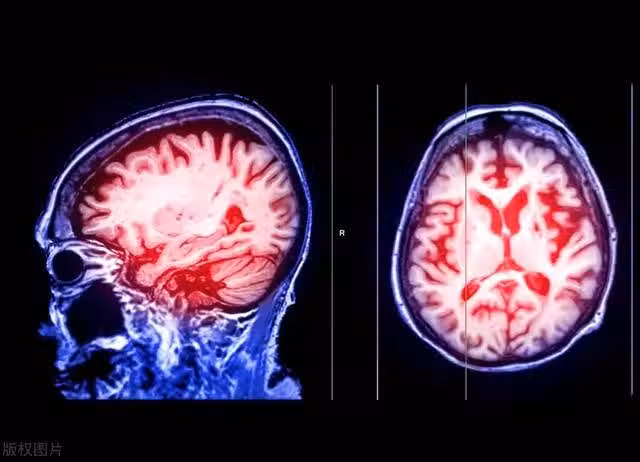

腦血管病是一種常見且具有嚴重後果的疾病,它包括腦梗塞和腦出血兩種主要類型。在這些疾病發生之前,往往會有一段時間的預警期,被稱為「止損期」。這個止損期是識別並干預潛在腦血管風險的黃金機會,因為錯過了這個時機,可能會導致不可逆轉的腦損傷。

腦血管病是指腦血管的功能異常引起的疾病,包括腦梗塞和腦出血。這些疾病的主要風險因素包括高血壓、高血脂、糖尿病、吸菸、肥胖以及家族遺傳等。這些因素會導致動脈硬化、血栓形成和血管破裂,從而引發腦血管病。

在腦血管病發生之前,通常存在一個預警期,也就是我們常說的「止損期」。在這個期間,人體會出現一些早期症狀和體徵,如頭痛、視力模糊、言語困難、手腳無力等。這些症狀可能是腦血管病的前兆,提醒我們存在潛在的腦血管風險。如果能夠及早識別並採取干預措施,就有可能避免或減輕腦血管病的發生。